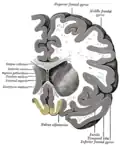

Коронарный срез мозга, прямая извилина отмечена жёлтым (внизу по центру)- Нижняя проекция мозга